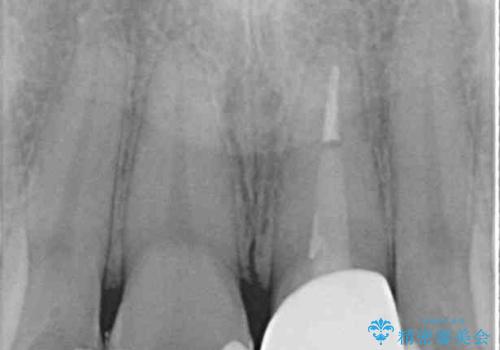

出っ歯に仕上がってしまった前歯 セラミッククラウンの作り替え

- 以前治療した時から、前歯のセラミックが張り出しているのが気になるとのことで来院された患者様です。

作り替えるべきが悩みましたが、どうしても気になるとのことで、処置を行うこととしました。

前歯1歯でのオールセラミッククラウンでは、オーダーメイドタイプのクラウンを選択していただき、周辺の歯と色調を合わせるようにするのですが、今回は既製タイプを選択されました。